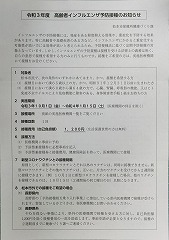

コロナCOVID-19 まとめ

③ 4回目コロナワクチン接種 22.07.30

② 3回目コロナワクチン接種 22.02.26

①1回目2回目コロナワクチン摂取済み票20210714=pdf